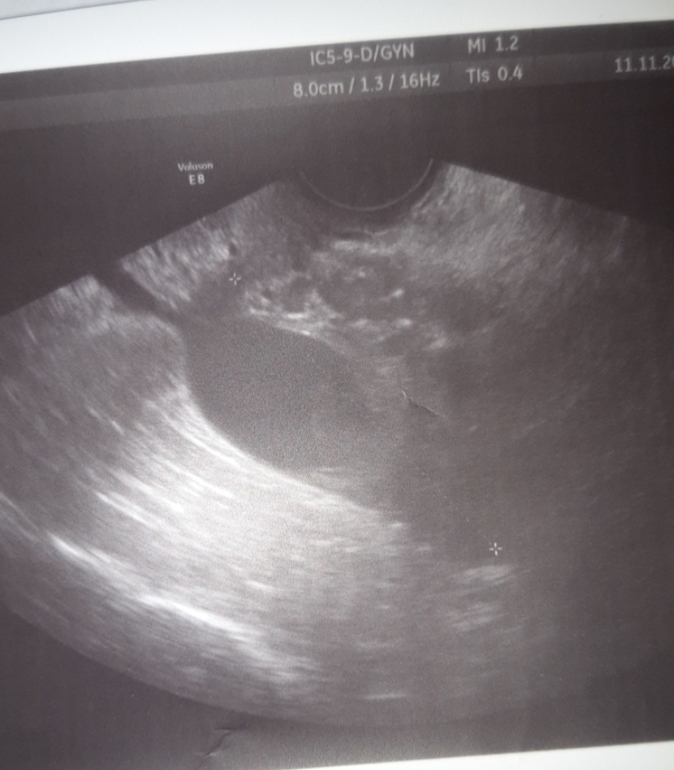

На последнем снимке фоликул. Желтое тело имеет другую структуру. И при фоликуле часто бывает жидкость в позадиматочном пространстве, в маленьком совсем количестве. Когда фолик лопается, там уже жидкости много

На всех фото одно и то же,просто я допускаю что овуляция была справа и давно,но узистка не смогла разглядеть правый яичник